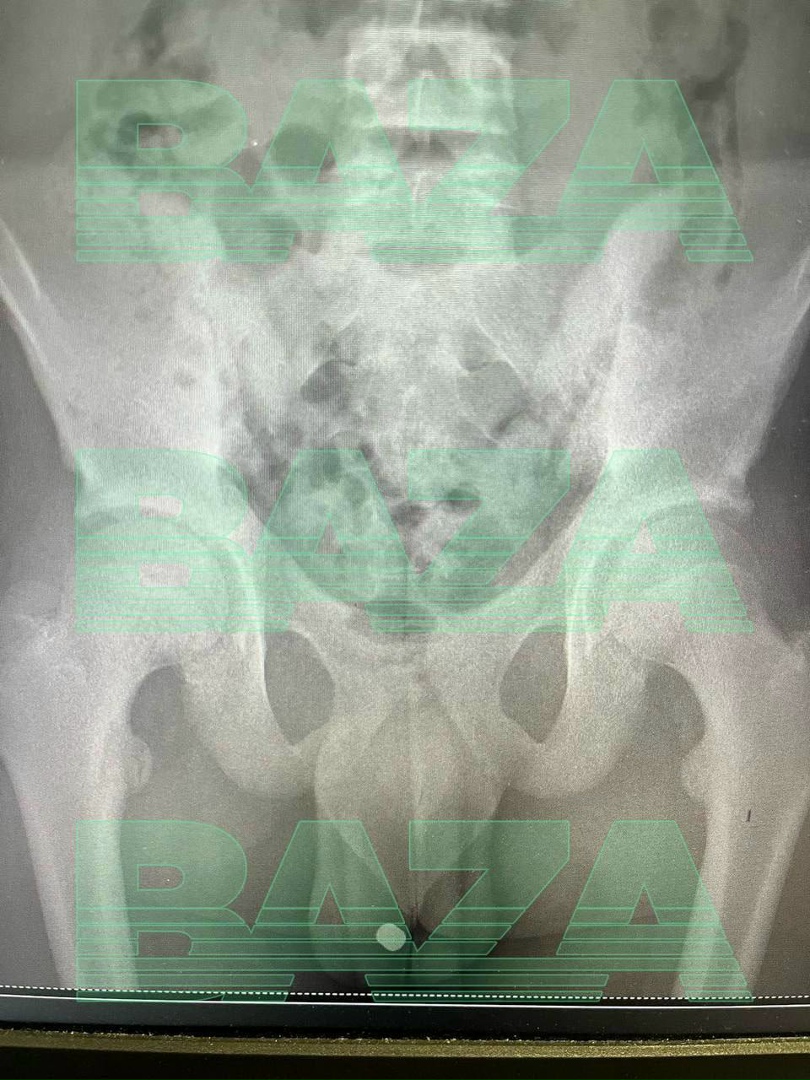

В Московской области зумер попал в больницу, потому что магнитные шарики в уретре не давали ему поссать.

Мочевой пузырь чуть не взорвался, но врачи вовремя спасли молодого экспериментатора. Объяснить свой поступок мальчик не смог